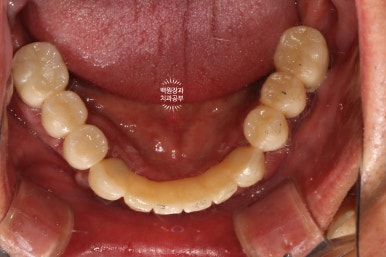

시간이 지나.. 최종 보철물을 만들어드리는 시간입니다.

약 한달간의 씹는 연습을 마치게 되면, 이제 본격적으로 최종 보철물을 제작해드리게 됩니다.

지르코니아 재질로 만들어진 크라운은 심미적으로도 유리하며, 그 단단함은 성인 남성이 넉넉히 사용하여도 깨지지 않을 정도에요.

치아 색이 약간 노랗다 생각하실수도 있으나, 피부색에 맞추어 제작되므로 너무 걱정하진 마세요!

오히려 너무 밝은 하얀 치아가 어색한 분도 많이 있으시기 때문입니다.

이렇게 보면 측면 모습도 상당히 괜찮고....

잘 보시면 치아와 치아 사이에 틈이 있는 것을 보실 수 있으실텐데요, 이 경계는 앞니 보철물/어금니 보철물의 경계로 추후에 보철물의 수리가 용이하기 하기 위함입니다. 더불어 치실을 쓸 수 있게 하는 공간으로 반드시 필요한 포인트!